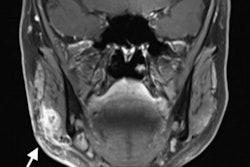

Face and lip fillers are proving increasingly popular, but they can cause serious health problems. In today's second article, German authors describe how MRI proved vital in treating a 62-year-old woman with infections and a 15-mm lesion resulting from injection with a facial dermal filler. Their case report deserves a close look.